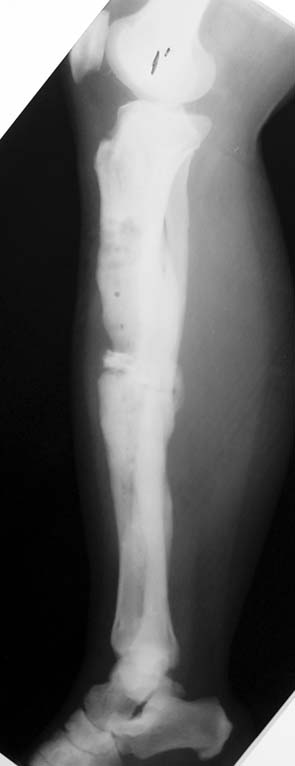

Tibia Osteomyelitis

Chronic Osteomyelitis

Chronic osteomyelitis leads to necrosis of bone and soft tissues. Dead bone is a nidus which hosts pathogenous microorganisms. Defence mechanisms of the host is usually not in optimum condition to deal with microorganisms. Antibiotics can’t reach the infection site because blood flow is disrupted. For these reasons, dead bone has to be completely removed by radical debridement.

Case 1